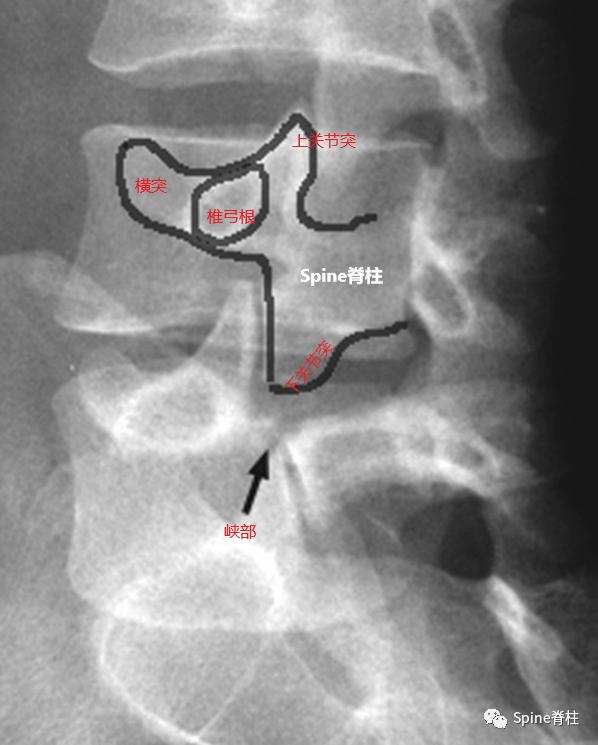

1. 腰椎峡部和峡部裂在X线斜位片的表现

腰椎峡部在腰椎斜位片上常比喻为苏格兰狗(Scotty dog)的脖子

椎弓崩裂征象:X线腰椎45°斜位摄片示上关节突轮廓似"狗耳",横突似“狗头/嘴”,椎弓根似“狗眼”,下关节突似“狗前肢”,关节突肩部或称峡部似“狗颈部”。椎弓峡部崩裂时,“狗颈部”可见裂隙。

腰椎斜位片上的苏格兰狗和断裂的脖子(峡部裂)

再回顾下腰椎斜位视角的模式图,圆圈处为峡部